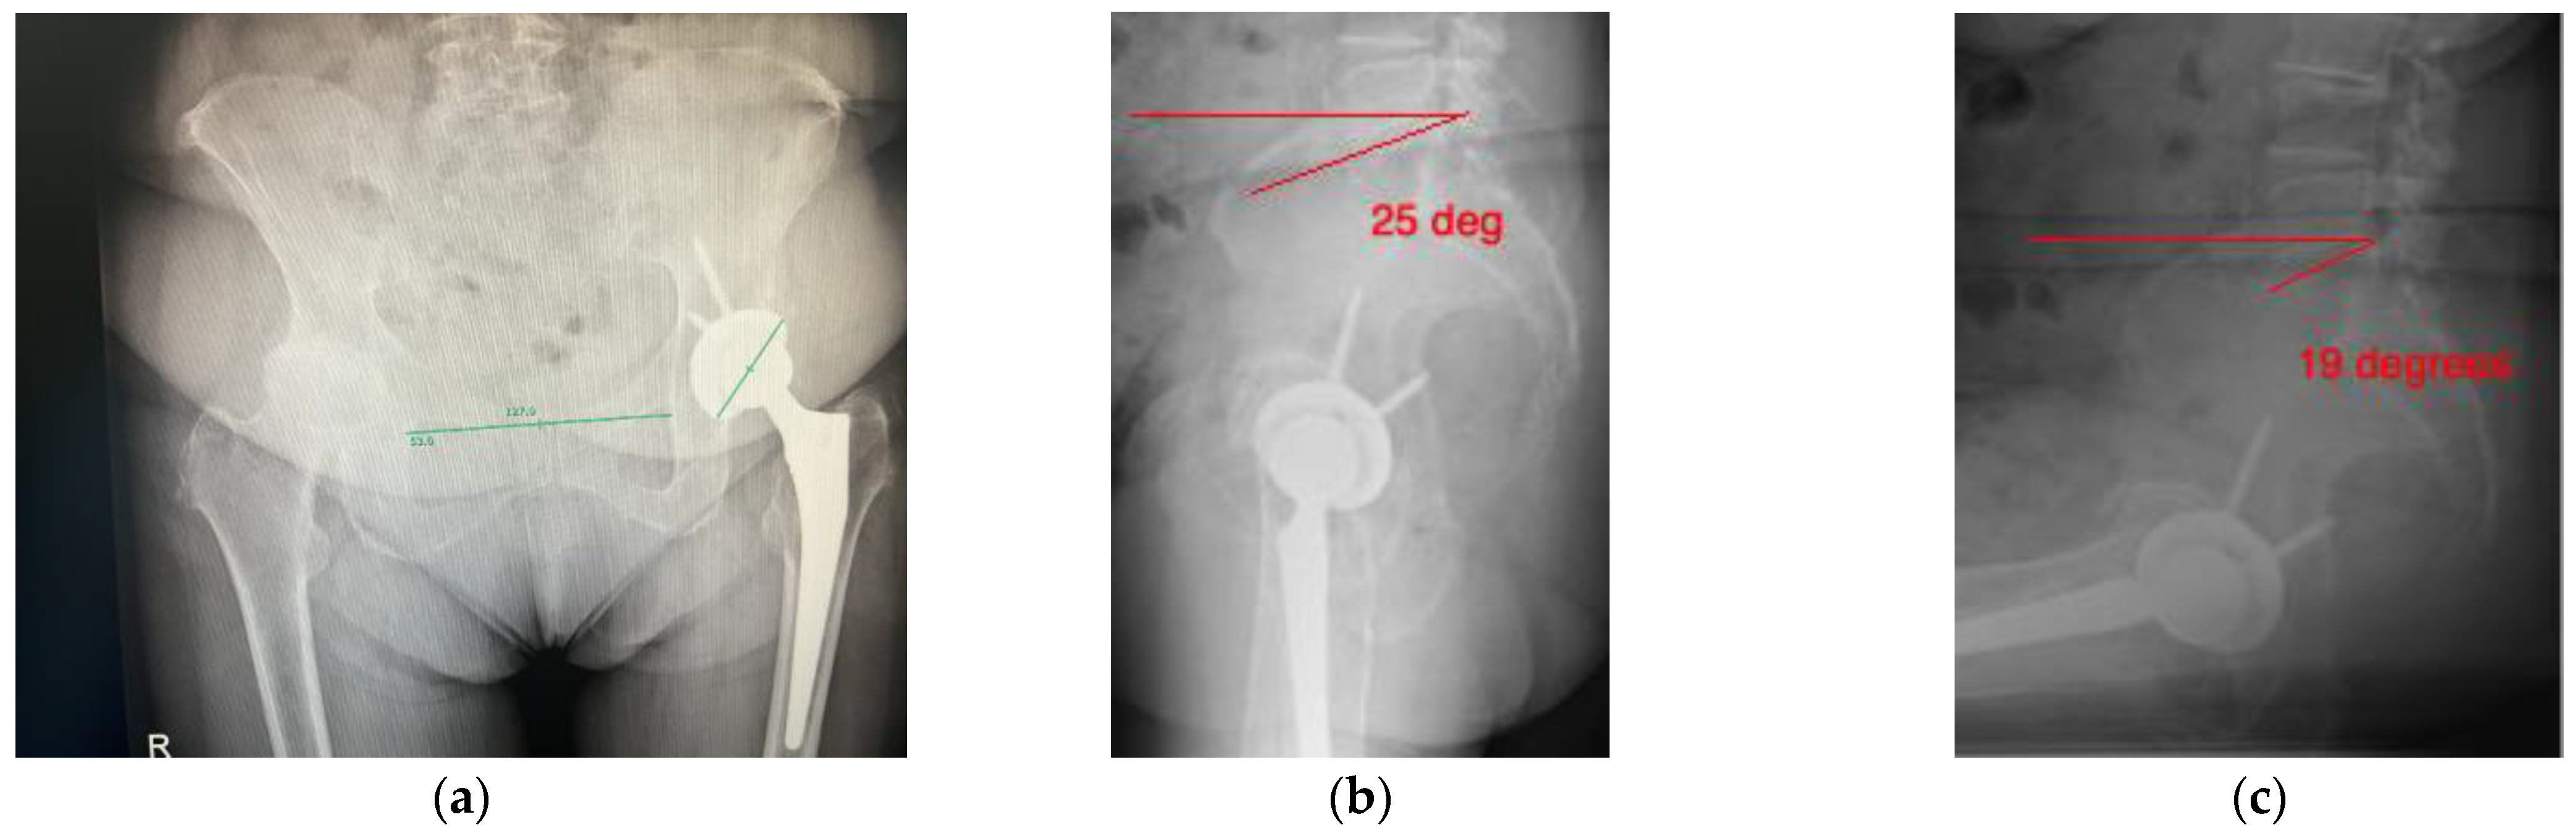

- The difference in sacral slope between standing and sitting radiographs was noted to be 6 degrees. According to the Stefl classification, this is stuck sitting, as the sacral tilt does not tilt anteriorly beyond 30 degrees with standing, indicating a high-risk patient (Figure 6a–c).